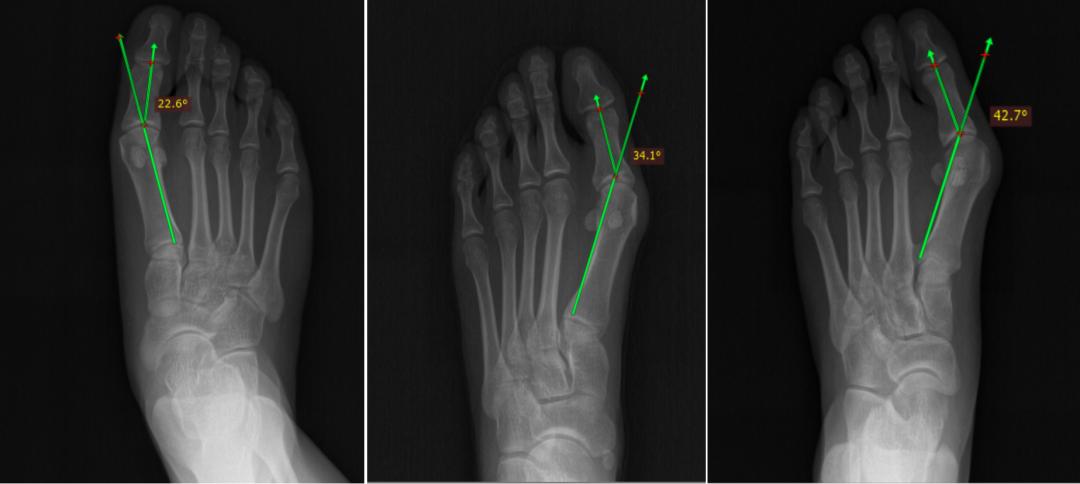

通过临床检查,拇外翻很容易被识别。拇外翻除了肉眼发现的拇指外偏、外移,还可以通过足部X线片检查,测量第1跖趾关节外翻角及第1、2跖骨间角等数据来进行程度分级,评骨继发病理改变。国内将拇外翻畸形分为轻度、中度和重度。轻度为:15°< 拇外翻角< 20°,第1、2跖骨间角<11°;中度为:20°<拇外翻角<40°,11°<第1、2跖骨间角<16°;重度为:拇外翻角>40°,第1、2跖骨间角>16°。

不同程度的拇外翻畸形